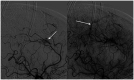

Cavernous malformations are angiographically occult vascular malformations. They are often associated with a developmental venous anomaly through poorly understood mechanisms. We present an unusual case of a gradually enlarging cavernous malformation associated with a developmental venous anomaly with arteriovenous shunting, suggesting venous hypertension or reflux as a potential cause of progressive growth.